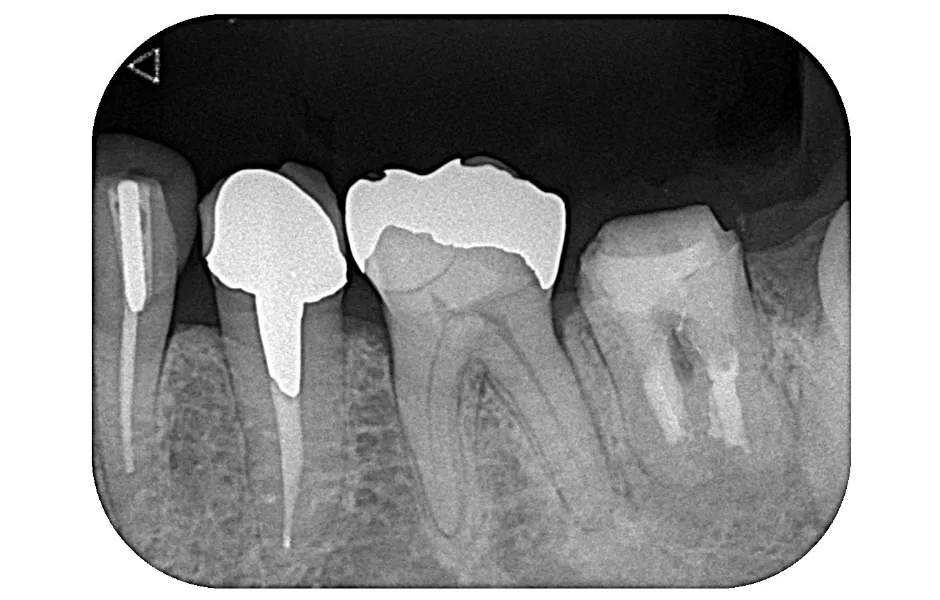

精密根管治療

神経まで進行して炎症を起こしている虫歯に対して行なう治療法になります。感染した神経を取り除き、しっかりと洗浄・消毒し、最後に薬剤を詰めて被せ物を装着します。

精密根管治療 -